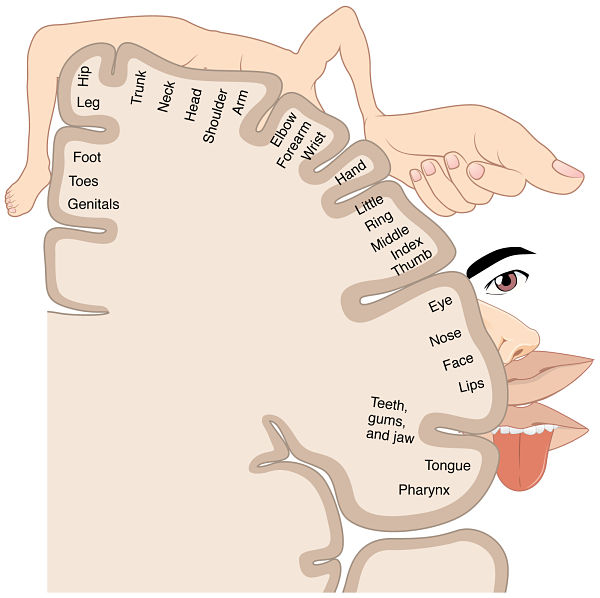

Cada información sensorial llega a un punto concreto de la corteza formando un homúnculo sensorial.

Como se puede observar, las áreas cerebrales correspondientes a los órganos no siguen el mismo orden con el que se disponen en el cuerpo, ni tienen una relación de tamaño proporcionada.

Las zonas corticales más grandes, en comparación con el tamaño de los órganos, son las manos y los labios, ya que en esta zona tenemos una alta densidad de receptores sensoriales.